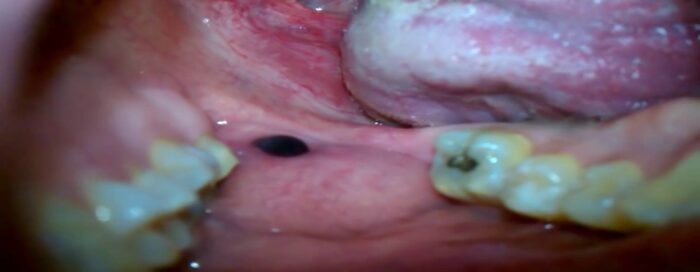

Causes Of A Black Spot Inside The Cheek

Looking in the mirror and seeing a black spot inside the cheek can be alarming, but is it something serious? The good news is that a dark spot inside your cheek is probably harmless. Consider these possible causes and see your dentist for a definitive diagnosis.

Amalgam Tattoos

If the spot inside your cheek is dark blue, gray or black, it could be a leakage from a dental filling. Amalgam tattoos aren't the permanent ink decorations on your skin that you can have done at a tattoo parlor. Amalgam is the silvery substance that your dentist uses to fill cavities, and it's made from a mixture of tin, zinc, mercury, copper and silver. Sometimes, after a dentist has filled a tooth, the filling mixture leaks, leaving behind a flat, painless dark spot that doesn't grow or change shape.

According to Brigham and Women's Hospital Division of Oral Medicine and Dentistry, amalgam tattoos are permanent, but they don't cause any harm. If the mark is inside your cheek, it's unlikely anyone will see it. However, if you think the spot looks unsightly, speak with your dentist about removal options.

The Oral Cancer Foundation lists several causes of dark spots inside cheeks that aren't related to cancer. For example, the inner lining of your cheek may just be patchily pigmented. You could have a benign melanotic macule, which is a spot similar to a freckle that can appear in the oral cavity. Alternatively, if you have put pencils in your mouth in the past, the graphite may have become embedded in your mouth lining, creating a dark spot.

Very rarely, a black or dark spot on the inside of the cheek could be a sign of oral malignant melanoma or another type of oral cancer. For this reason, it's always worth seeing your dentist if you notice an abnormal spot in your mouth that doesn't go away, bleeds or grows larger. Your dentist can diagnose the cause of the black spot through an examination, and they may take a sample to send for analysis.